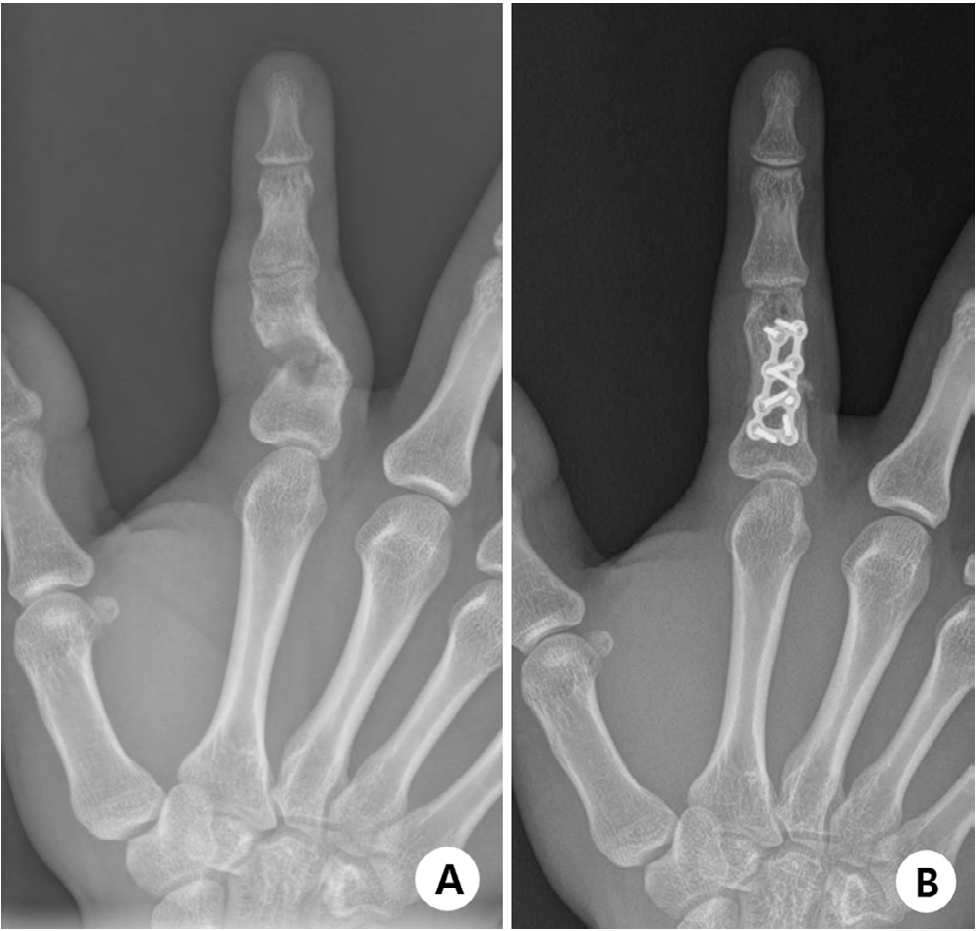

There are two general techniques to correct intraarticular malunions: For malunions less than 8–10 weeks old where the old fracture line is still definable, an osteotomy through the fracture can reverse the deformity and improve articular congruence [27]. However, this requires manipulating and fixing small, unstable articular fragments, which theoretically risks biological breakdown and fixation failure [31,38]. For chronic malunions where the fracture line is no longer visible, special osteotomy techniques are needed to reduce the articular surface [38]. Teoh et al. [39] described a technique of wedge osteotomy in the intercondylar region to create a larger condylar fragment. This allows easier correction of articular malunion and fixation of a larger fragment [39]. It theoretically reduces risks of fixation failure, nonunion, and osteonecrosis [39]. A supracondylar closing wedge osteotomy just proximal to the collateral ligament insertion has also been described with good results [2,31,40]. For the most severe deformities with arthropathy, arthrodesis and arthroplasty are excellent options [23]. Bony mallet injuries can cause intraarticular malunions of the DIP joint [41]. The main concern with these injuries is the extension lag of the DIP joint and consequent hyperextension of the PIP joint, resulting in a swan neck deformity [41]. Incongruity can also induce DIP arthropathy. In those cases, arthrodesis in 5°–10° of flexion is most optimal in hand function [41].

• 31. Chen KJ, Huang YP, Lo IN, Huang YC. Corrective osteotomy for distal condylar malunion of the proximal phalanx in adolescents: comparison of K-wire and locking plate fixation. J Hand Surg Eur Vol 2022;47:935-43.ArticlePubMedPDF

Fig. 3. (A) A case with atrophic nonunion and consequent reduction loss. (B) Atrophic nonunion can be treated surgically by stable fixation and autogenous cancellous bone graft.